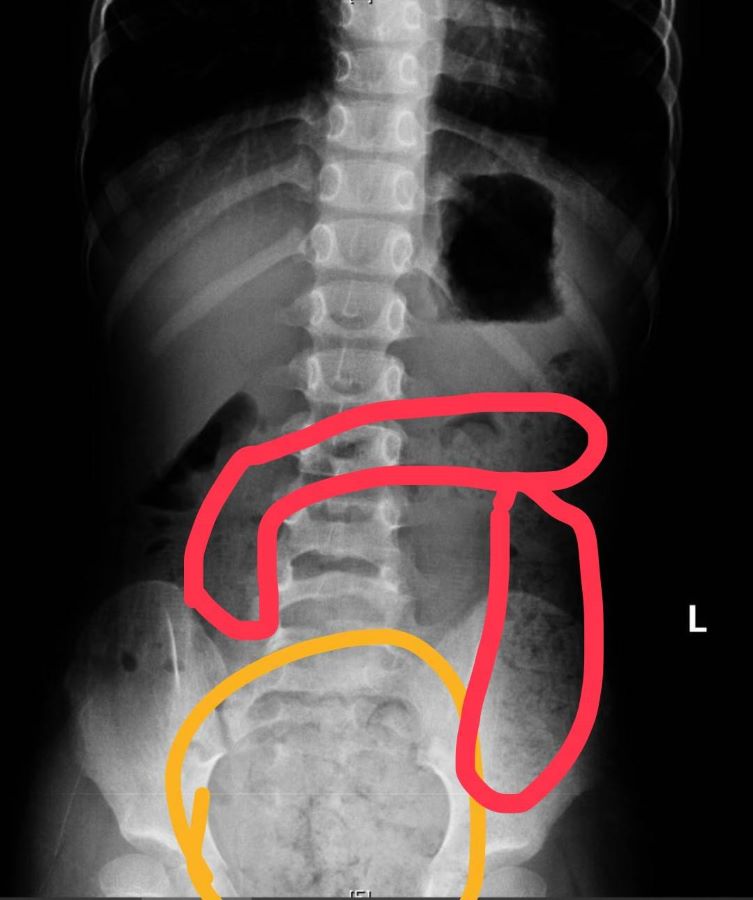

【記者 王雯玲/高雄 報導】一名11歲小五男生因為腹痛、冒冷汗、嘴唇發紫、手腳冰冷被送來急診,經問診、觸診及腹部X光檢查後診斷是便秘,為他灌腸後解出很多大便,症狀也隨即緩解。媽媽說男孩習慣邊大便、邊玩手機,都是被罵上太久才匆忙沖馬桶、從廁所出來,自己也都不清楚是否有大出來或有沒大乾淨!

▲11歲男生X光片,畫圈部分為積糞。